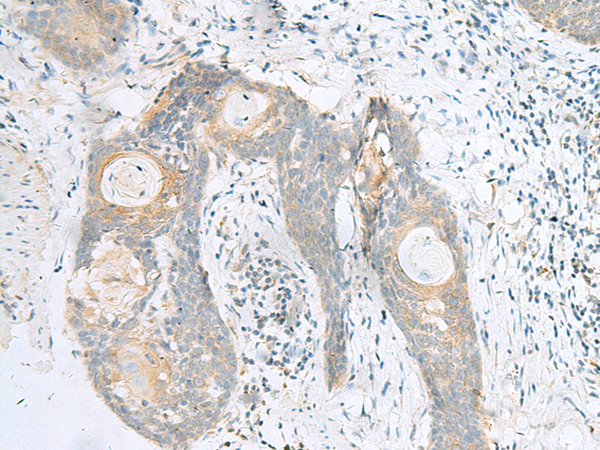

IHC positive control:

Human tonsil and Human esophagus cancer